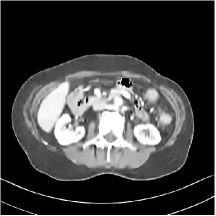

First, we study transform training based on Mayo Clinic data. As shown in Fig. 6, seven slices obtained at regular dose from three patients are used for transform learning. The number of pixels . Similar to the phantom experiments, overlapping patches are extracted with a patch stride. The number of overall training patches is about . We set for ST, , , for MARS2, , , , , for MARS3, , , , , , , , , for MARS5, , , , , , , , , , , , , for MARS7. The iteration number in Algorithm 1. Fig. 7 illustrates the learned transforms obtained with Mayo Clinic data. Different from the XCAT phantom case, these transforms up to MARS5 display more complex features and structures. The rich features of the MARS models better sparsify the training images over layers compared to the single-layer model (ST).

III.C.2. Simulation Framework, Reconstruction Results, and Comparisons

The synthesized low-dose clinical measurements are simulated from regular-dose images at a resolution of mm with a fan-beam CT geometry corresponding to a monoenergetic source at incident photon intensity . The sinograms are of size . The width of each detector column is mm, the source to detector distance is mm, and the source to rotation center distance is mm. We reconstruct images of size with the pixel size being mm mm.

We conducted experiments on one test slice used for parameter tuning (L067-slice 120) and four independent test slices (L109-slice 90, L192-slice90, L333-slice140, L506-slice 100) of the Mayo Clinic data. For PWLS-EP, we ran iterations using relaxed OS-LALM and set regularization parameter . We used the same as the phantom experiments for Algorithm 2. The process of selecting a general set of reconstruction parameters () for the Mayo Clinic test slices is identical to that for the XCAT phantom in Section III.B.2. The selected regularization parameter and the parameters that control the sparsity of the coefficient maps are for ST, , , , , for MARS2, , , , , , , for MARS3, , , , , , , , , , , for MARS5, and , , , , , , , , , , , , , , for MARS7, respectively.

Figs. 8, 9, 10, and 11 show the reconstructions of the four independent slices using the FBP, PWLS-EP, PWLS-ST, PWLS-MARS2, PWLS-MARS3, PWLS-MARS5, and PWLS-MARS7 schemes, respectively. Additional Mayo Clinic experimental results of the parameter tuning case (Fig. 15) are shown in the supplementary document. Table 1 lists the RMSE and SSIM values of reconstructions of the four independent test slices, with the best values bolded. Generally, the five and seven layer models provided the best RMSE and SSIM values. They outperform the single-layer model by HU in RMSE on average. However, the MARS5 and MARS7 models perform similarly. In order to strengthen the benefits of the multi-layer model, Table 2 lists the RMSE of the reconstructions in four different ROIs (shown in the reference of Fig. 11) with seven methods for slice 100 of patient L506. By observing the reconstructed images, we see that although the ST model achieves a cleaner reconstruction result than FBP and PWLS-EP, it still sacrifices some sharpness of the central region and suffers from loss of details. The deeper models have a somewhat more positive effect in terms of maintaining subtle features, which is clearly more essential to clinical diagnosis. Furthermore, as we will discuss later, after considerable parameter tuning, we found that the information contained in residual maps is gradually decreased with the number of layers, eventually vanishing at some layer, which suggests that very deep unsupervised models might not offer significantly better image quality.